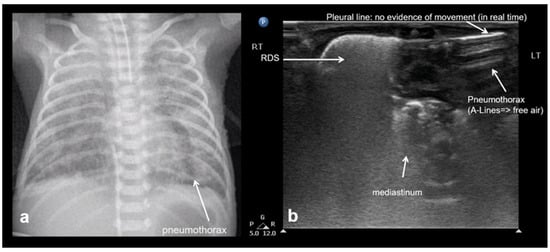

3.1.7. Lung Point Sign

The “lung point” or “lung point sign” is a highly specific lung sonographic sign which helps in the diagnosis of pneumothorax and can also facilitate the assessment of pneumothorax severity. In particular, the severity of pneumothorax depends on its position relative to the anatomical lines that define the regions of the chest. In LUS, the “lung point” is defined as the boundary between the area without normal lung sliding (i.e., pneumothorax) and the area where normal lung sliding is present (normal lung) (Figure 8) [4,12,15,16,25,26].

Figure 8.

Lung point sign: The transition point between the aerated lung with coalescent B-lines (which probably represents respiratory distress syndrome) which are absent in pneumothorax and the area with A-lines (transparent arrow) but without lung sliding (absent in pneumothorax in real-time scanning).